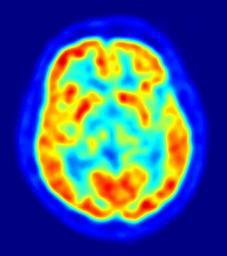

MAKE A MEME View Large Image PET-image.jpg This is a transaxial slice of the brain of a 56 year old patient male taken with positron emission tomography PET The injected dose have been 282 MBq of 18F-FDG and the image was generated from a 20 minutes measurement with an ...

Keywords: PET-image.jpg This is a transaxial slice of the brain of a 56 year old patient male taken with positron emission tomography PET The injected dose have been 282 MBq of 18F-FDG and the image was generated from a 20 minutes measurement with an ECAT Exact HR+ PET Scanner Red areas show more accumulated tracer substance 18F-FDG and blue areas are regions where low to no tracer have been accumulated Own 2010 Jens Maus http //jens-maus de/ Positron emission tomography